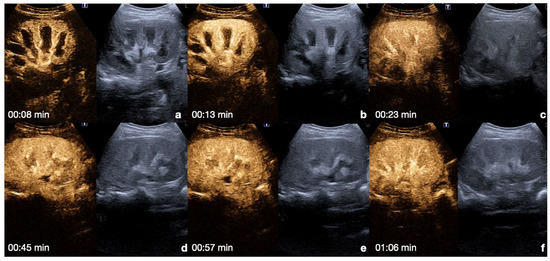

Spleen: the arterial phase starts 12–20 s after the injection. This phase shows irregular enhancement, similar to what is seen during MDCT, making it difficult to define any parenchymal injury. The venous phase starts 40–60 s after the injection. This phase provides adequate organ injury detection as the healthy parenchyma appears with a homogeneous enhancement for 5–7 min (Figure 7) [13,26,30].

Figure 7.

CEUS findings in a normal spleen (a–d). Note the progressive physiological enhancement after contrast medium injection. Adopted from ref. [30], 2021, Iacobellis, F.; et al.